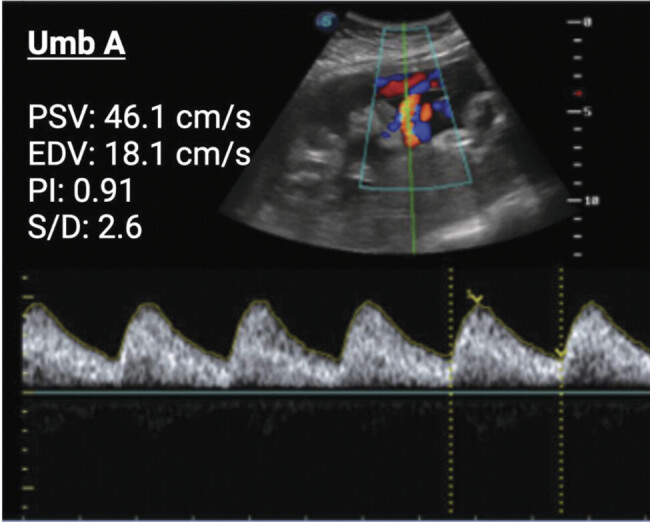

Preeclampsia is a multiorgan vascular disease complicating approximately 8.5 million pregnancies worldwide annually and is a leading cause of maternal and neonatal mortality. The impact is especially severe in Latin America, where maternal deaths attributable to preeclampsia are 2.5 times higher than in any other region. Bolivia is particularly affected due to economic and environmental challenges, including high altitude, which increases the risk of fetal growth restriction and hypertensive disorders of pregnancy. Early and accessible diagnostic tools are required to maximize patient care and improve reproductive outcomes in limited-resource settings. This report details a case from Bolivia of rapid-onset severe preeclampsia with liver rupture in the third trimester; the patient required multiple surgical interventions for recurrent liver bleeding and extended hospitalization in the intensive care unit (ICU). She delivered a preterm, growth-restricted infant with signs of acute hypoxia by emergency cesarean section. Notably, 2 weeks before ICU admission, abnormal uterine artery and maternal hemodynamic measurements were detected, without other signs of preeclampsia. The patient had previously been healthy and was considered low risk. Both mother and newborn survived. This case underscores the value of combining uterine artery Doppler with maternal hemodynamics to identify high-risk pregnancies early and prevent life-threatening complications.